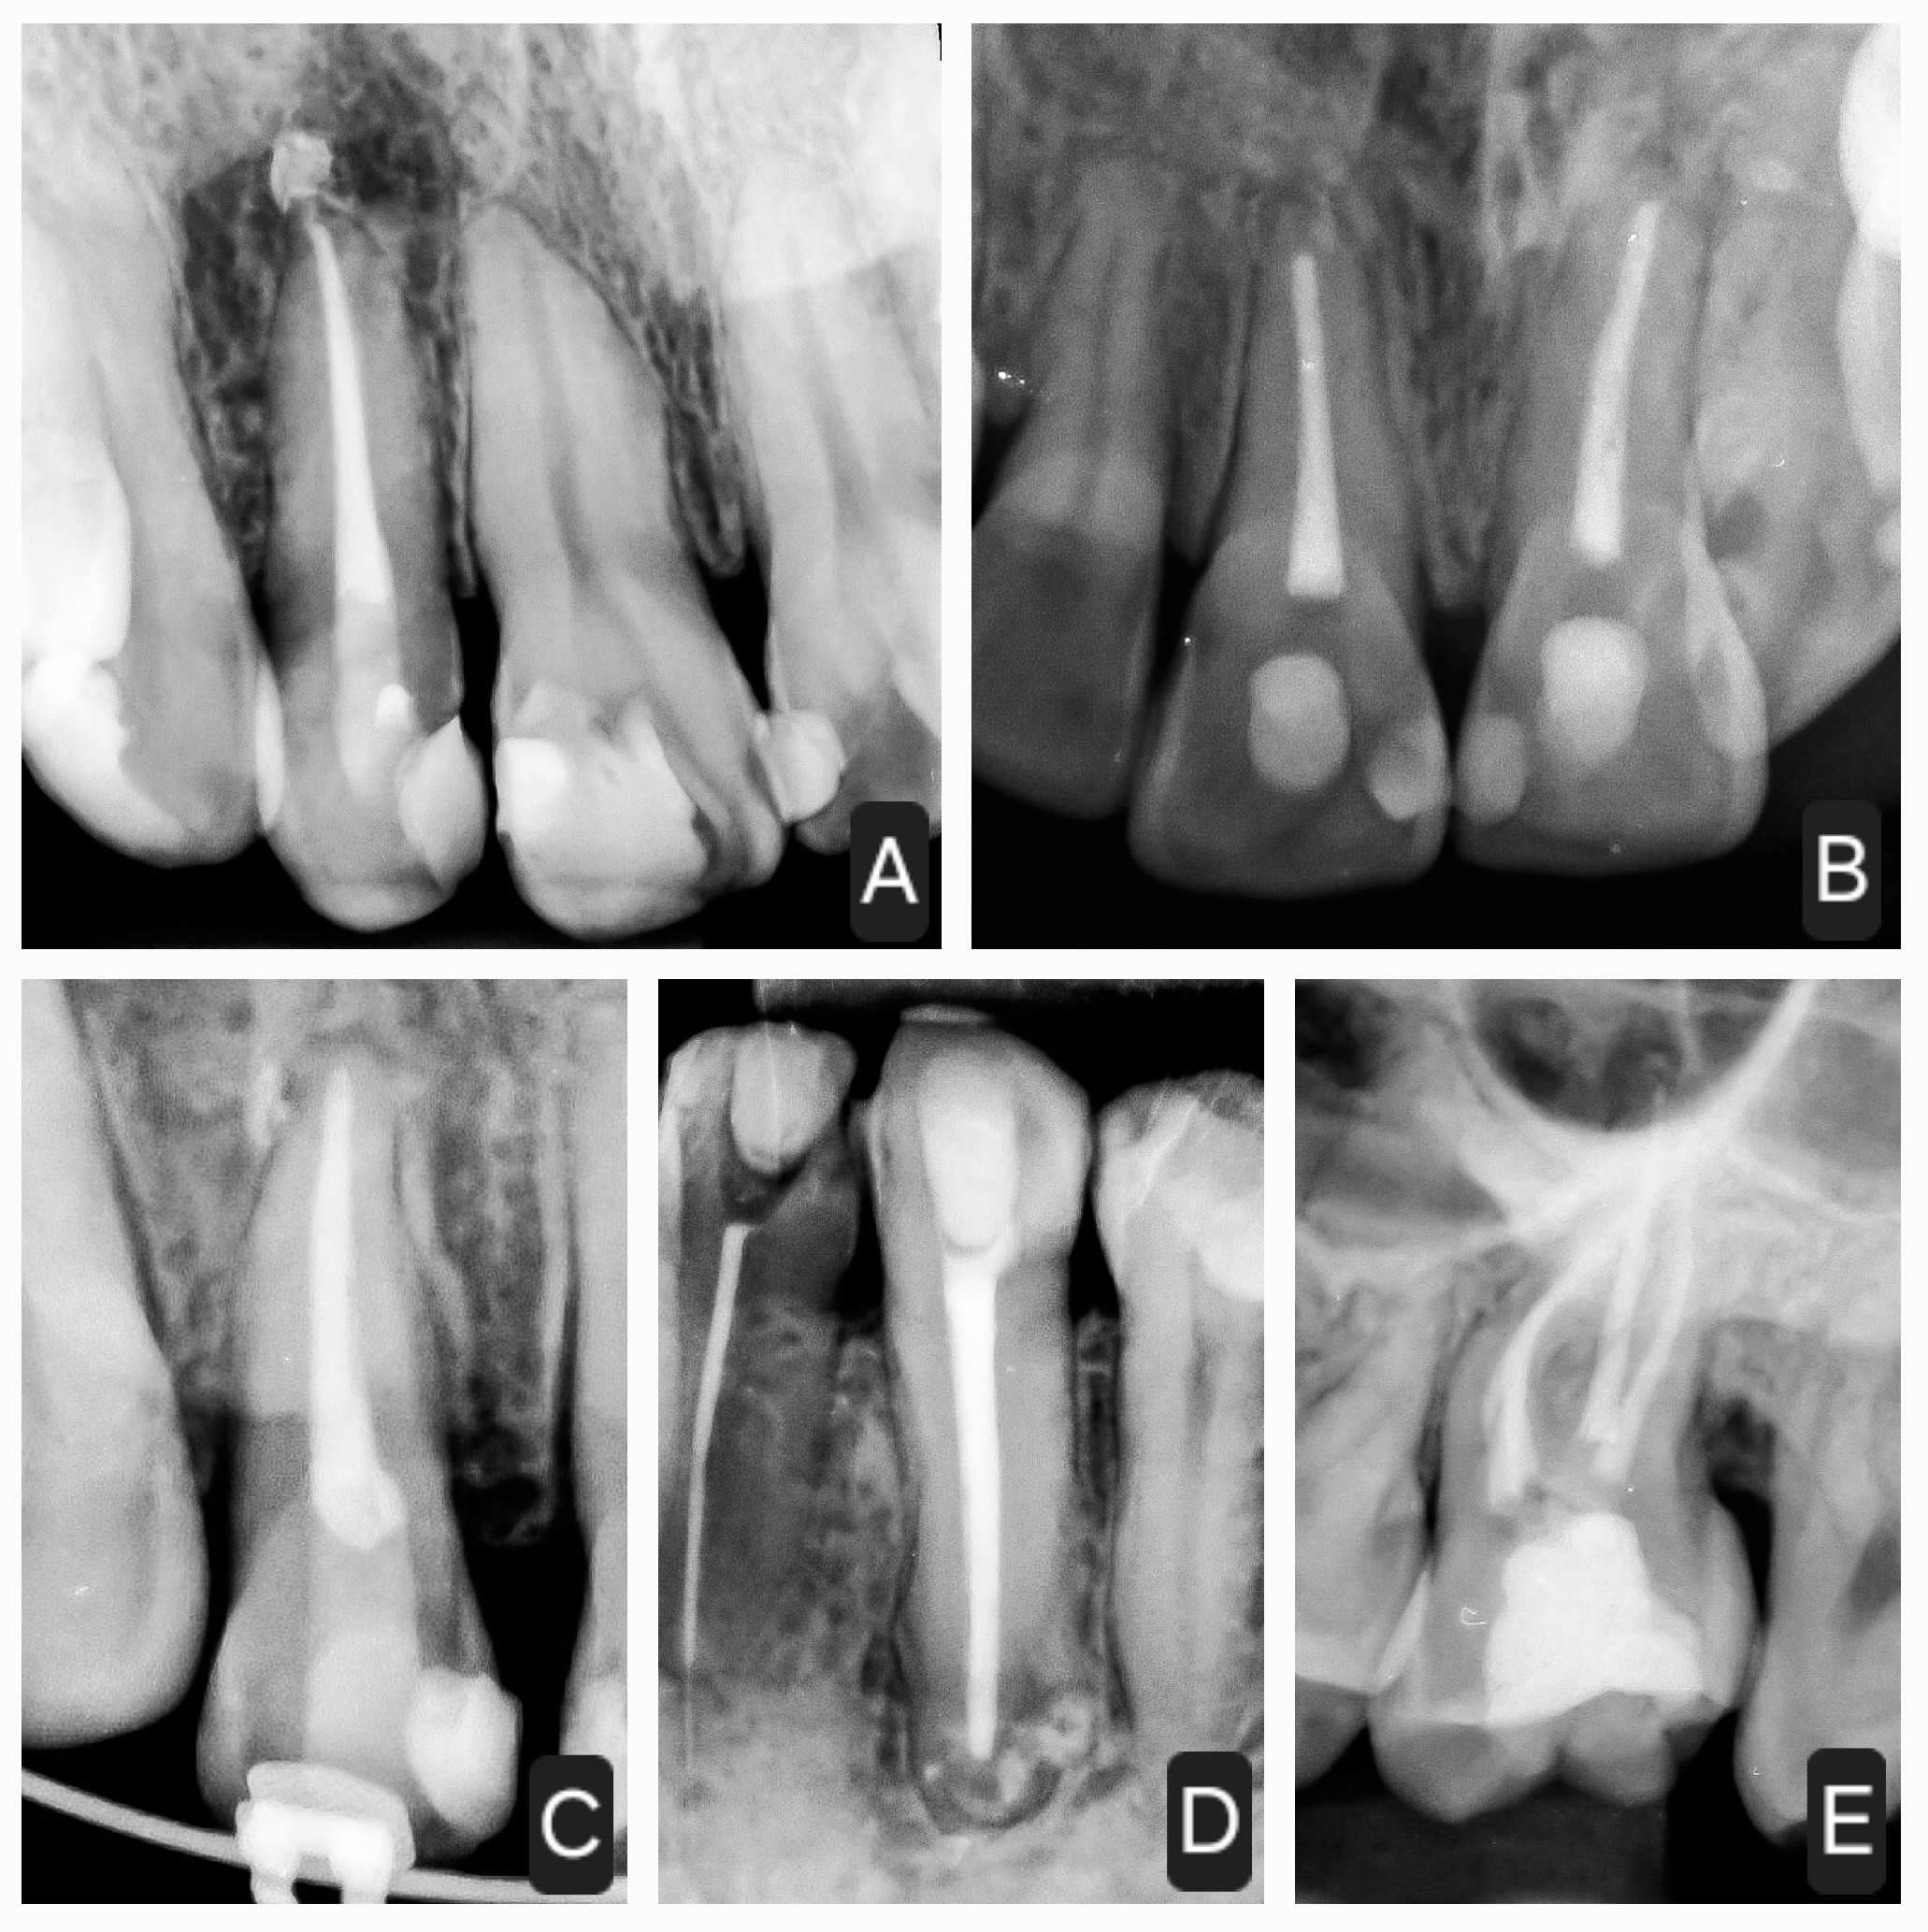

2.6. Control Periapical X-rays